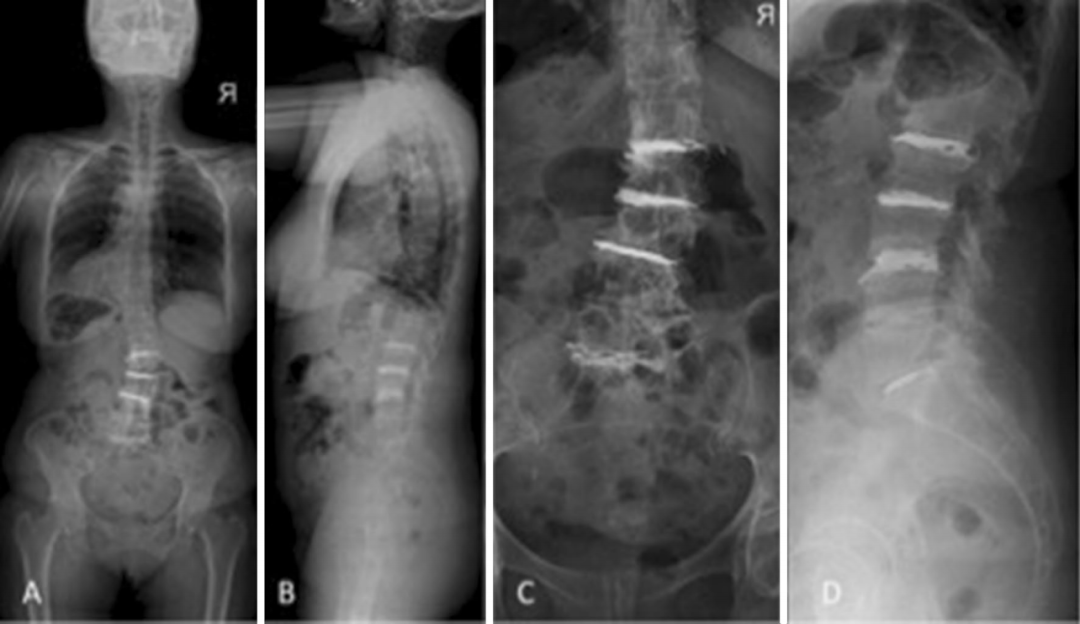

图: 与典型病例相似的另一退变性侧凸患者,术前存在手风琴现象,经多节段PCD术后冠状位得到10°的纠正且恢复部分腰椎前凸

回顾性分析PCD治疗54例严重椎间盘退变伴/不伴退行性侧凸的病例资料,手术步骤参考上述的技术报道,术后最少随访1年,VAS和ODI评分均显著改善,腰椎前凸和冠状位Cobb角得到部分纠正。平均手术时间38min,平均住院时间1.2天。